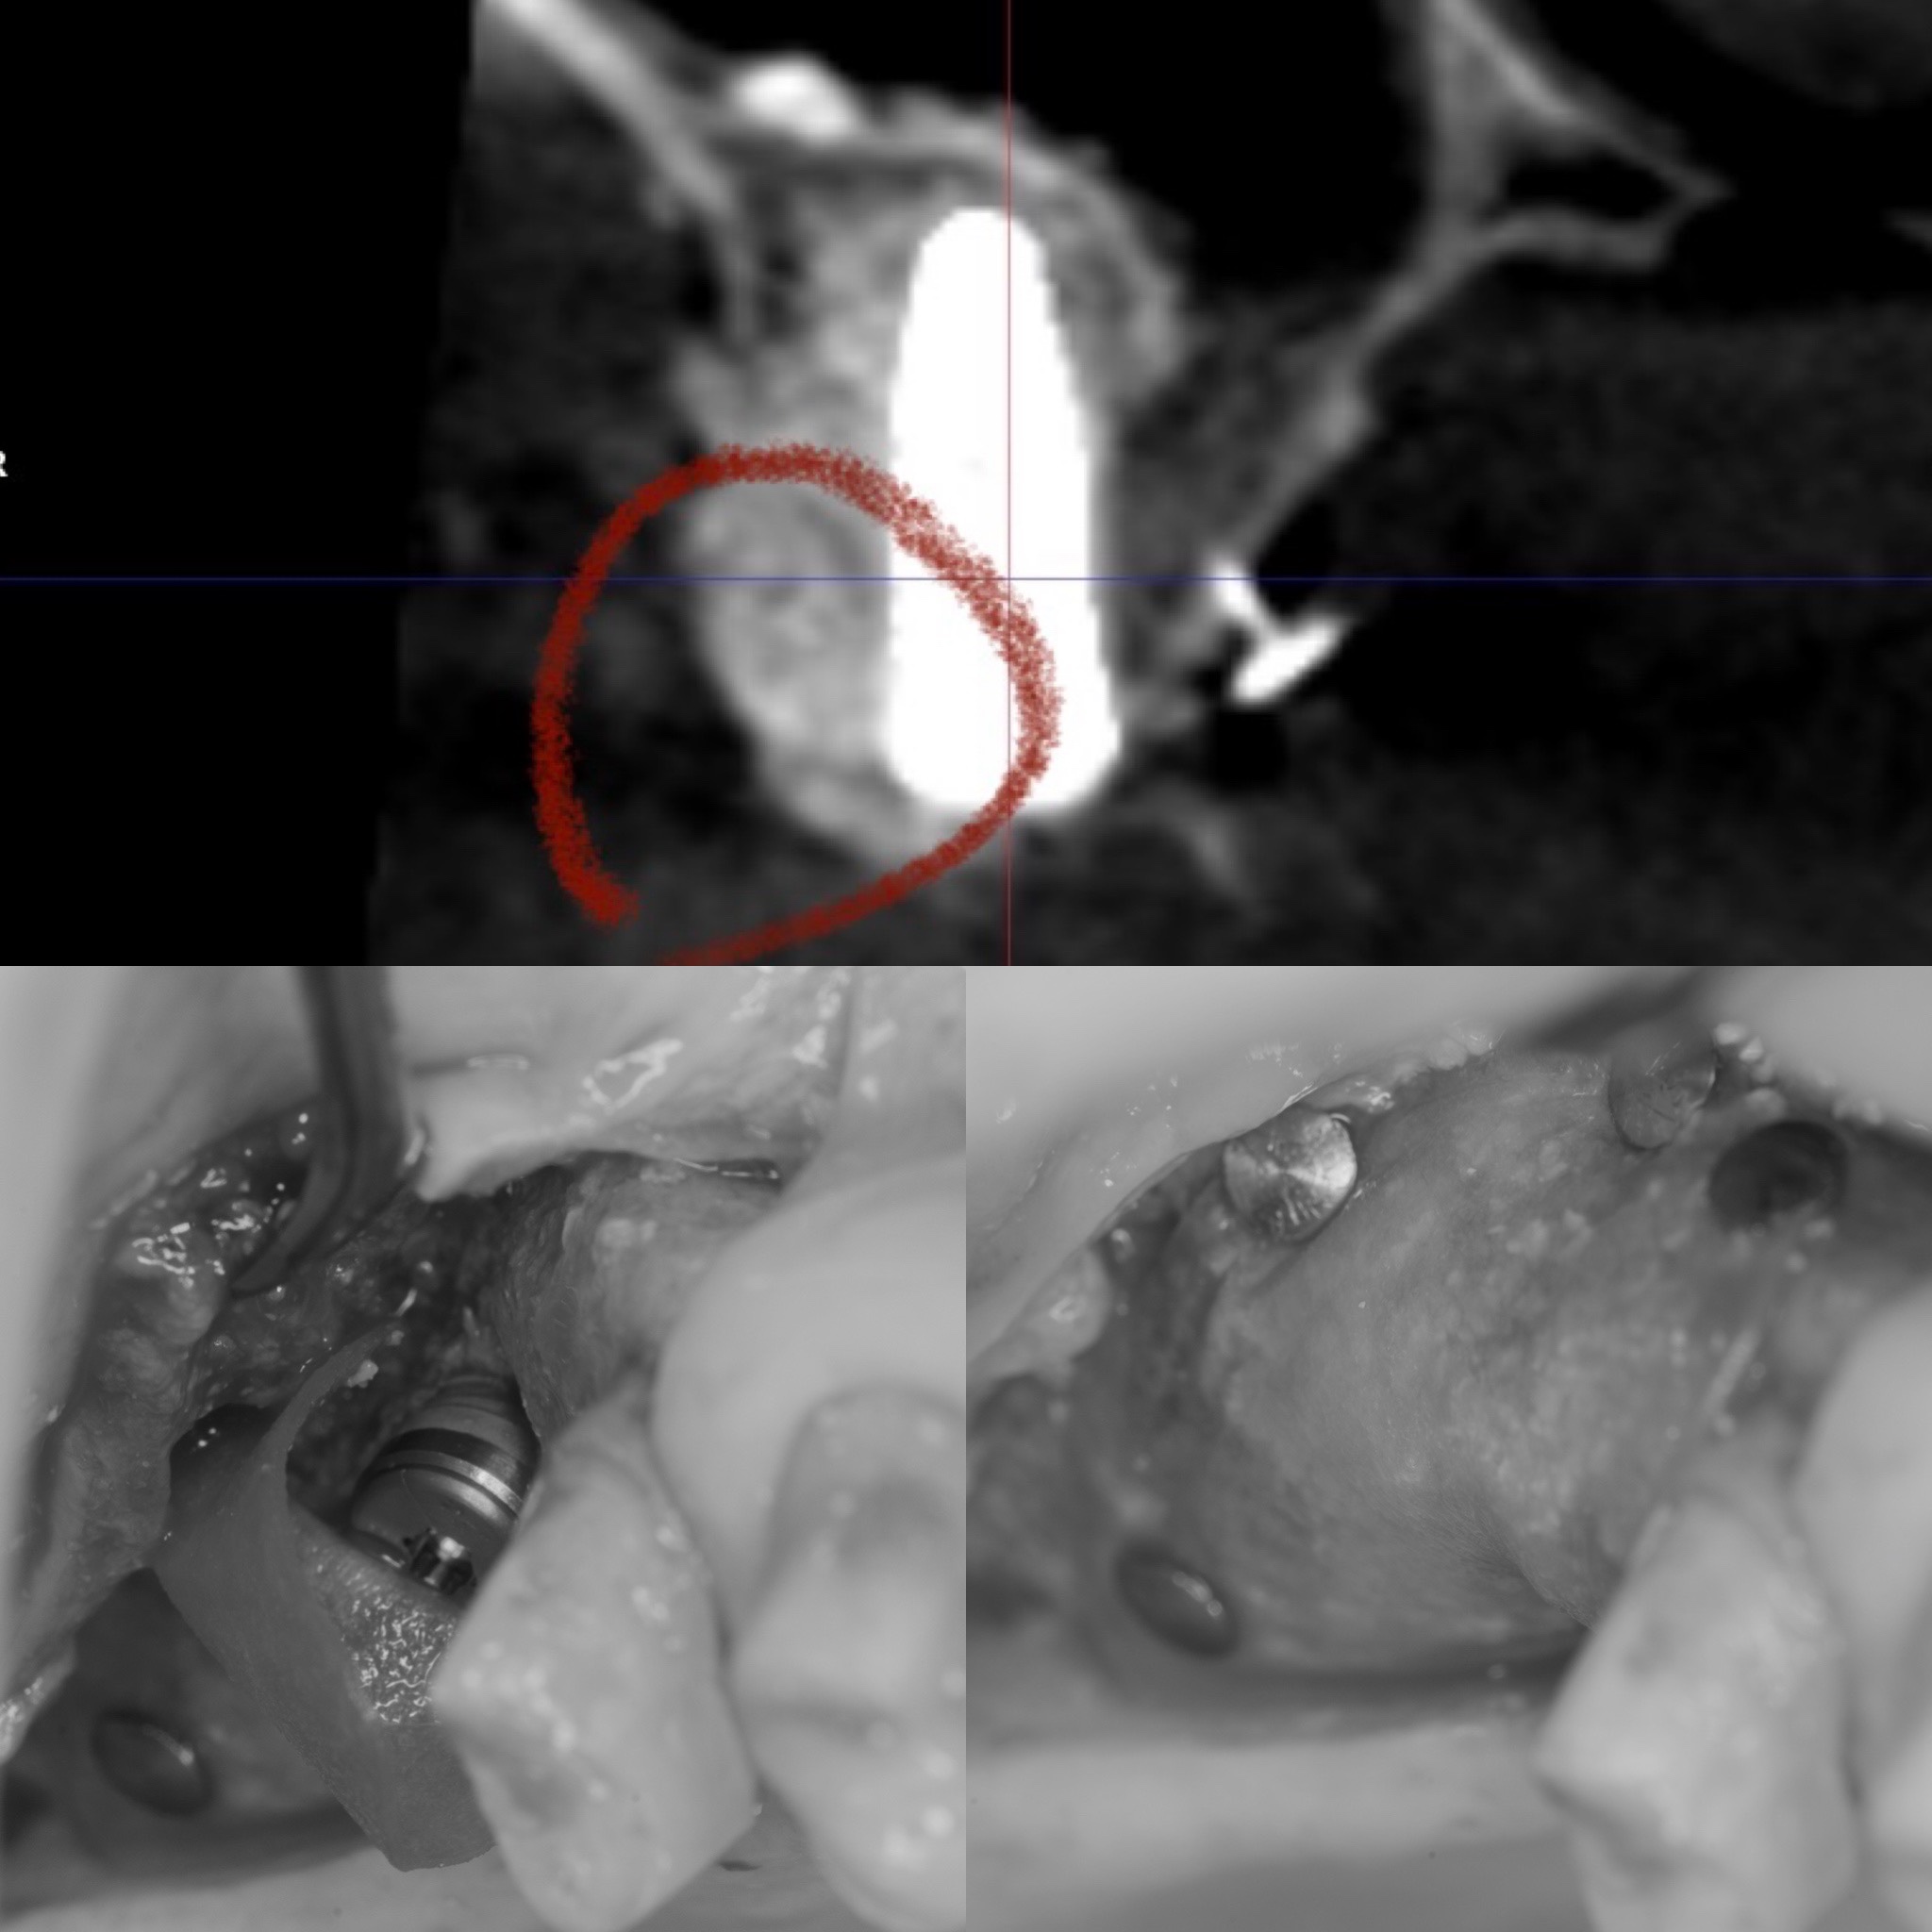

白いのがインプラントでマークした部分が、骨を再生させた部分です🦴

下のが実際の写真で、骨を追加して、メンブレンという膜をピンでしっかり固定する事により、3〜6ヶ月で成熟した骨になります✨